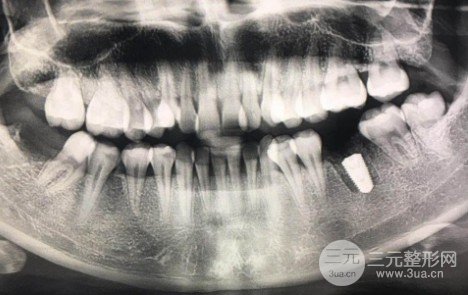

三个月前。拔掉了我右下第六颗牙。这颗牙几年前就蛀了,之后又补了两次。较后一颗补了200块的牙值日5年。不知道什么时候中心破了。直到周围的牙龈有脓包突出,严重发炎,可能会侵蚀牙槽骨。在与医生反复沟通后,我不得不拔掉这颗牙。种植牙前,我在各种平台上看了很多帖子,很多专业人士介绍了修复方法的选择,种植牙的优点,种植牙的程序和注意事项。

下午先拍了CT,接下来,计划安排好了,手术开始了,主任医师是外科医生,整个手术由三个医生完成。用消毒水漱口两分钟后,我躺在那把椅子上,灯光刺眼。消毒过的棉花被涂在嘴巴周围和整个鼻子,用一块绿色的布覆盖着手术(这块布有名字吗?),只露出口腔。因为眼睛在绿色的布下面,手术看不到医生一路上使用过什么工具。更多医院对比、价格优惠、口碑评价,点击在线免费咨询哟

拔掉被剪断的线,拆线是较简单和疼痛感较轻的。爱护牙齿,感激每天的所作所为,不拖延的尽快处理牙齿问题。牙根植入已经一个多月了,现在能舔到缺牙中间一个硬硬的东西。它就像一个螺丝钉,上面有一个钉帽。打开这个盖子是内螺纹的,当时用来固定牙冠。现在是漫长的等待时间。当人工牙根与我,的牙槽骨一起生长时,医生说将在大约3-5个月后拥有一个牙冠。